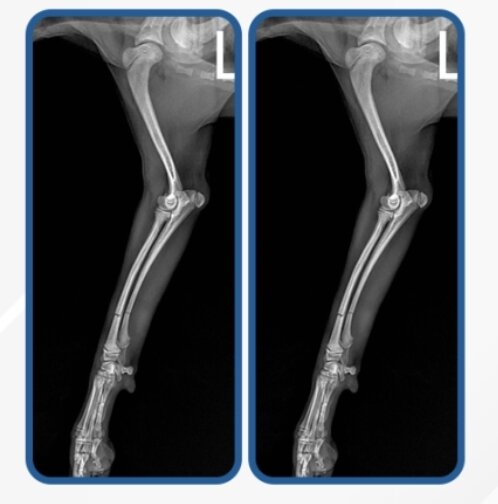

본문 이미지 - 성인 무릎 높이에서 뛰어 내려 착지하다 골절이 발생한 반려견 방사선 검사 이미지(로얄동물메디컬센터 제공) ⓒ 뉴스1

성인 무릎 높이에서 뛰어 내려 착지하다 골절이 발생한 반려견 방사선 검사 이미지(로얄동물메디컬센터 제공) ⓒ 뉴스1